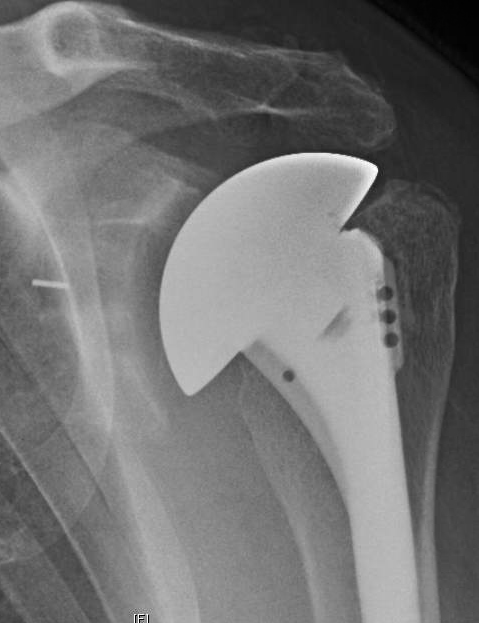

Here are the 2 year films of this shoulder after conservative shoulder arthroplasty using a standard glenoid component without attempts to modify glenoid version. The humeral head is centered in the prosthetic glenoid. At two years after surgery the patient was able to perform all 12 functions of the Simple Shoulder Test.

Note that sufficient bone stock remains to perform a revision total or a reverse total shoulder arthroplasty shoulder these procedures become necessary in the future of this young person.